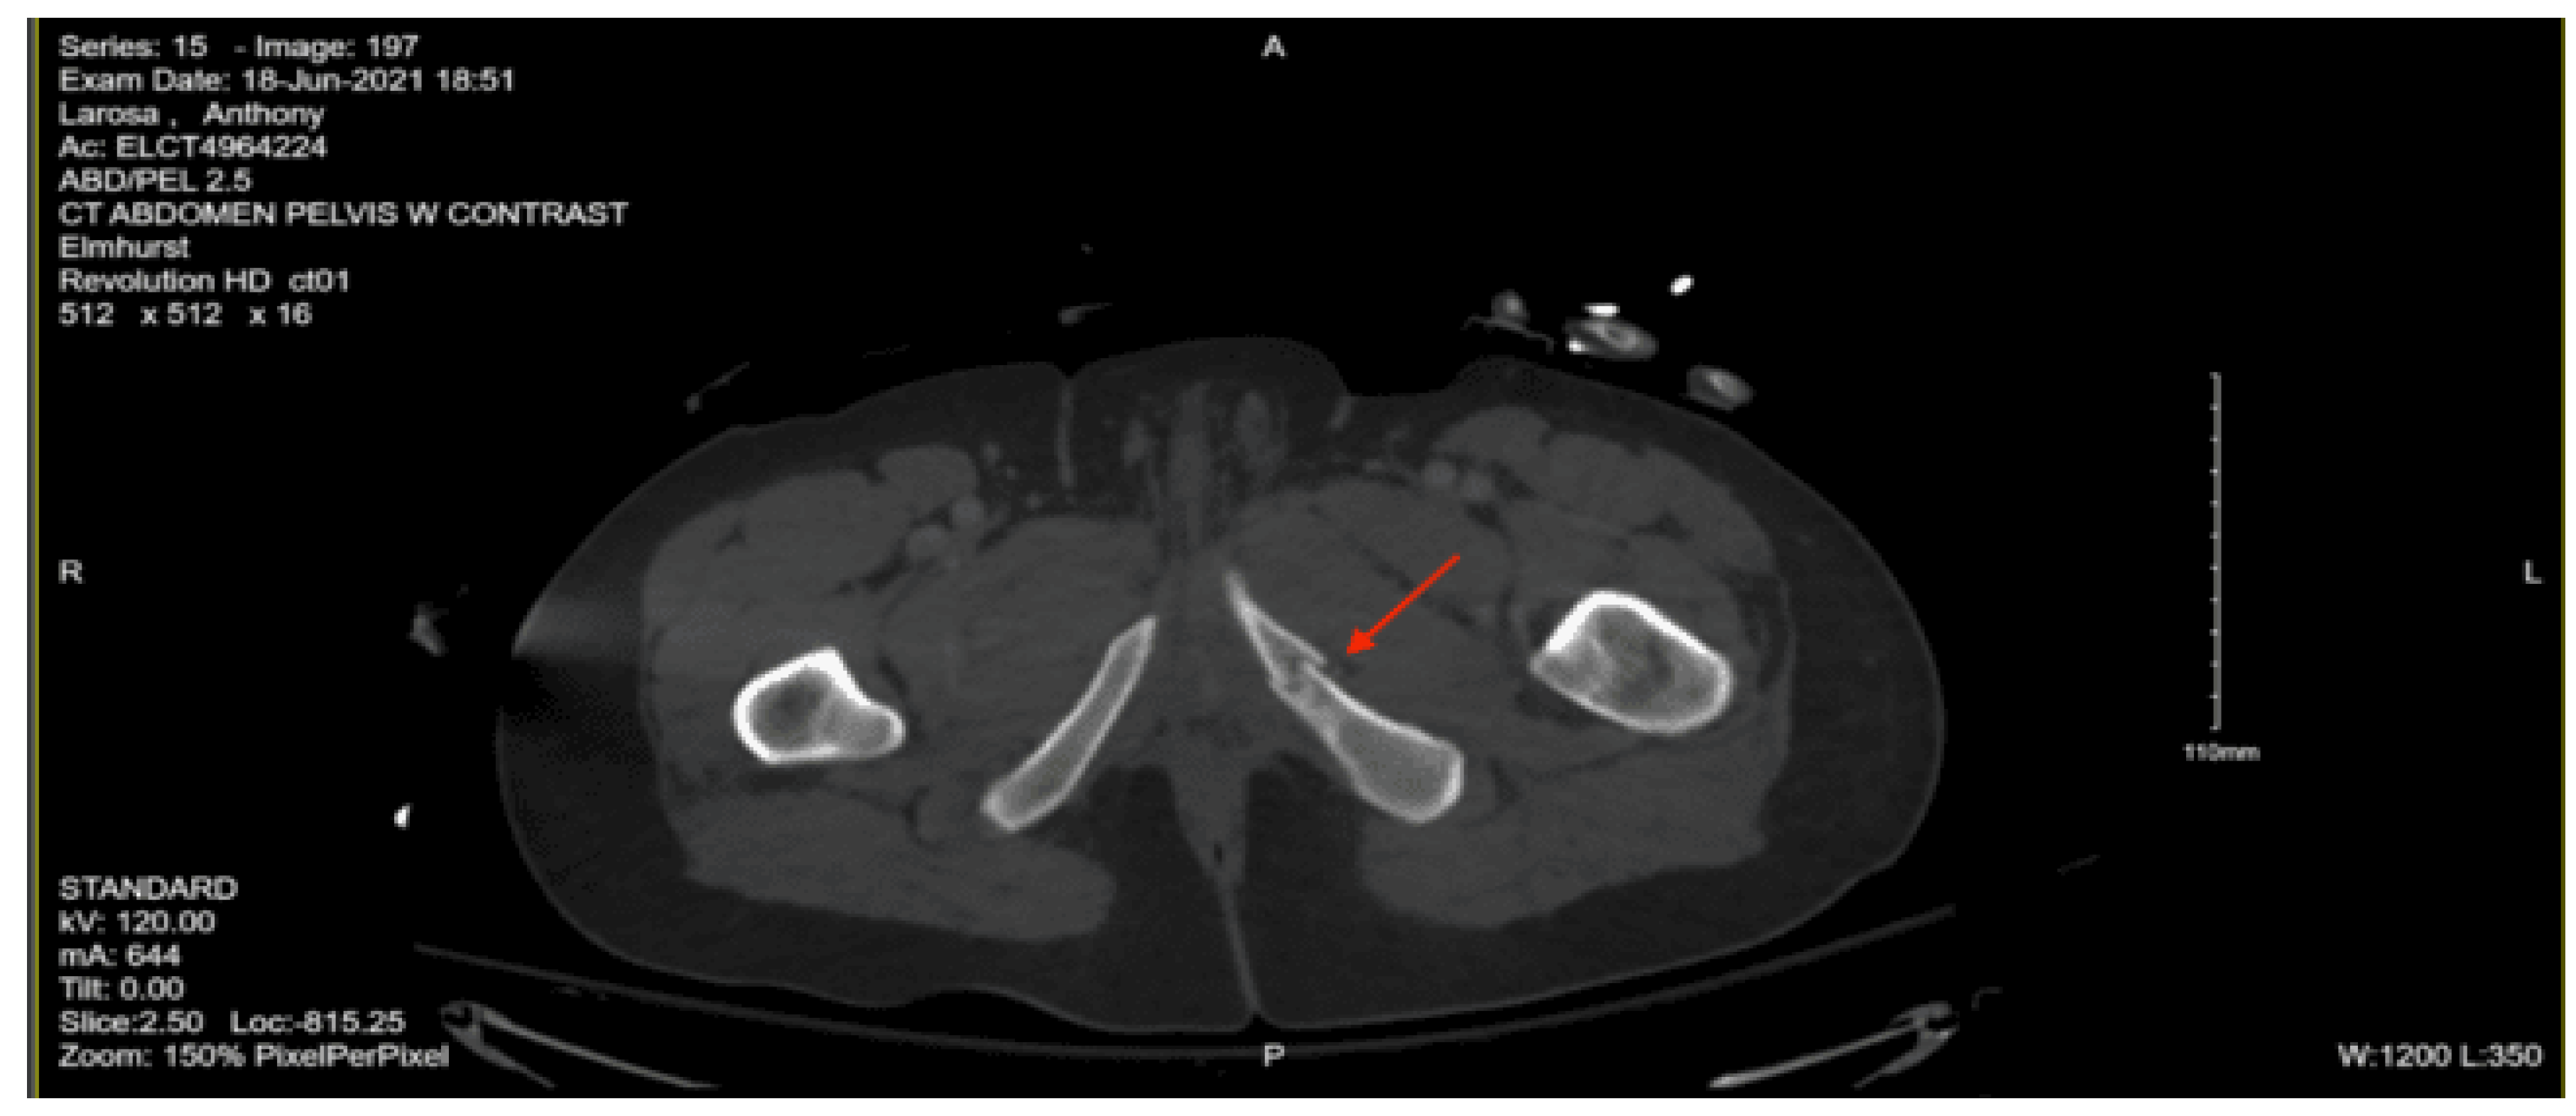

Imaging as shown in Figure 19 and Figure 20:

CT Abdomen Pelvic with contrast: No evidence of acute visceral injury. Redemonstration of fractures of the proximal right femur. Fractures of the right inferior petrous and right transverse processes of L2 and L3.

CT femur w/o contrast, Right: Comminuted fracture of the proximal subtrochanteric right femur with posterior medial displacement. Nondisplaced fracture of the right inferior pubic ramus.